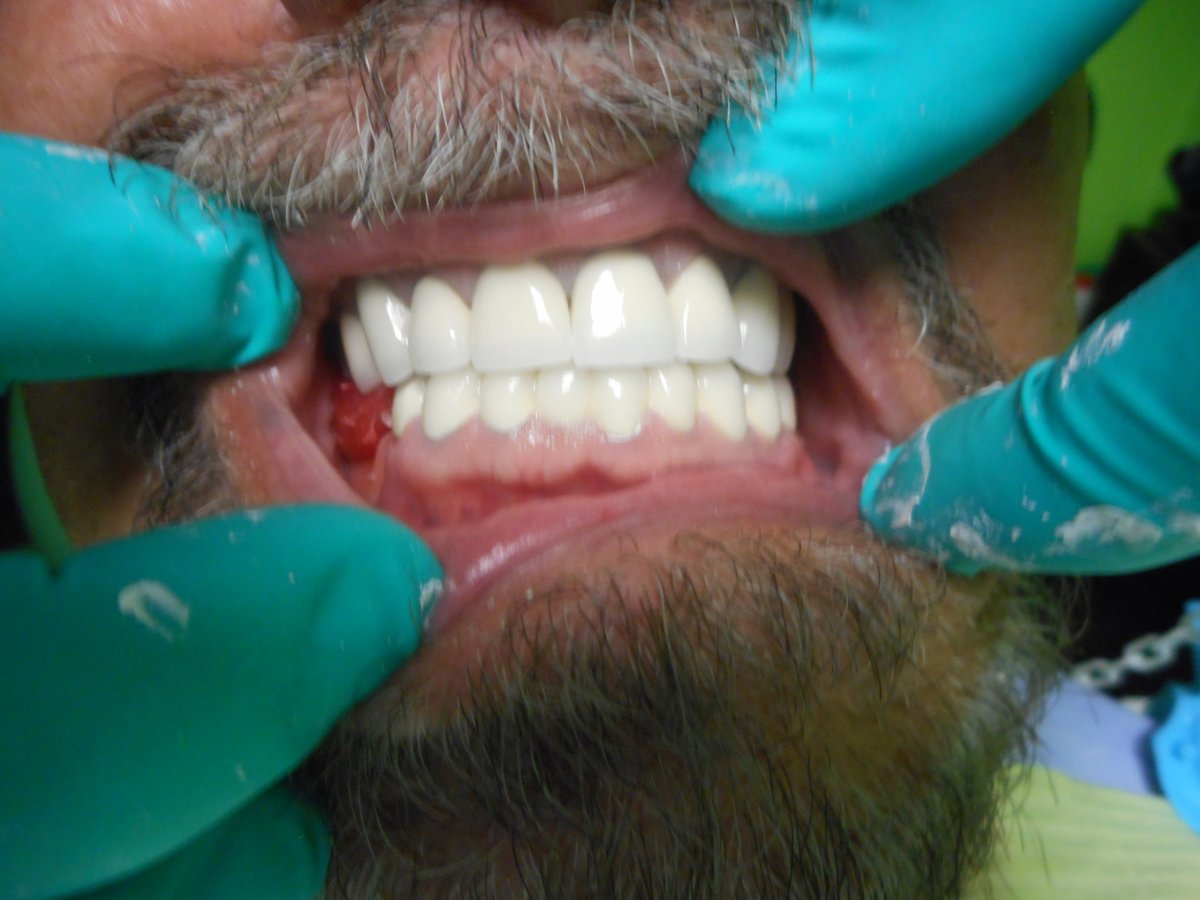

About Alpha Dental Implant Center Dental care can be affordable. See what we can do for you. FREE exam and estimate. We are in Nuevo Progreso Mexico, The Safest border town in Texas. Just across the border of Weslaco, Texas., We are a Full-Service Dental Clinic, But We Specialize in Dental Implants. All done, By a Qualified Dentist in his field, With Quality Materials, at a Reasonable Price. 2019 Harvard Dental Boston Internationa... (Show more)

| Dental Crowns | $400 |

| Dental Implants | $13,999 |